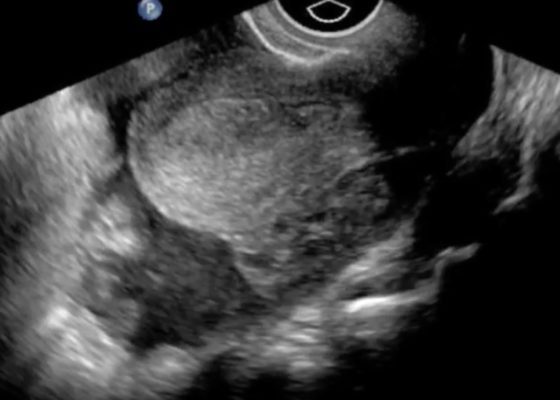

Ruptured Ectopic Pregnancy

DOI: https://doi.org/10.21980/J8SG6TThe patient’s serum beta-hCG was 5,637 mIU/mL. The transvaginal ultrasound showed an empty uterus with free fluid posteriorly in the pelvis and Pouch of Douglas (00:00). A 4.5 cm heterogeneous mass was visible in the left adnexa concerning for an ectopic pregnancy (00:10).